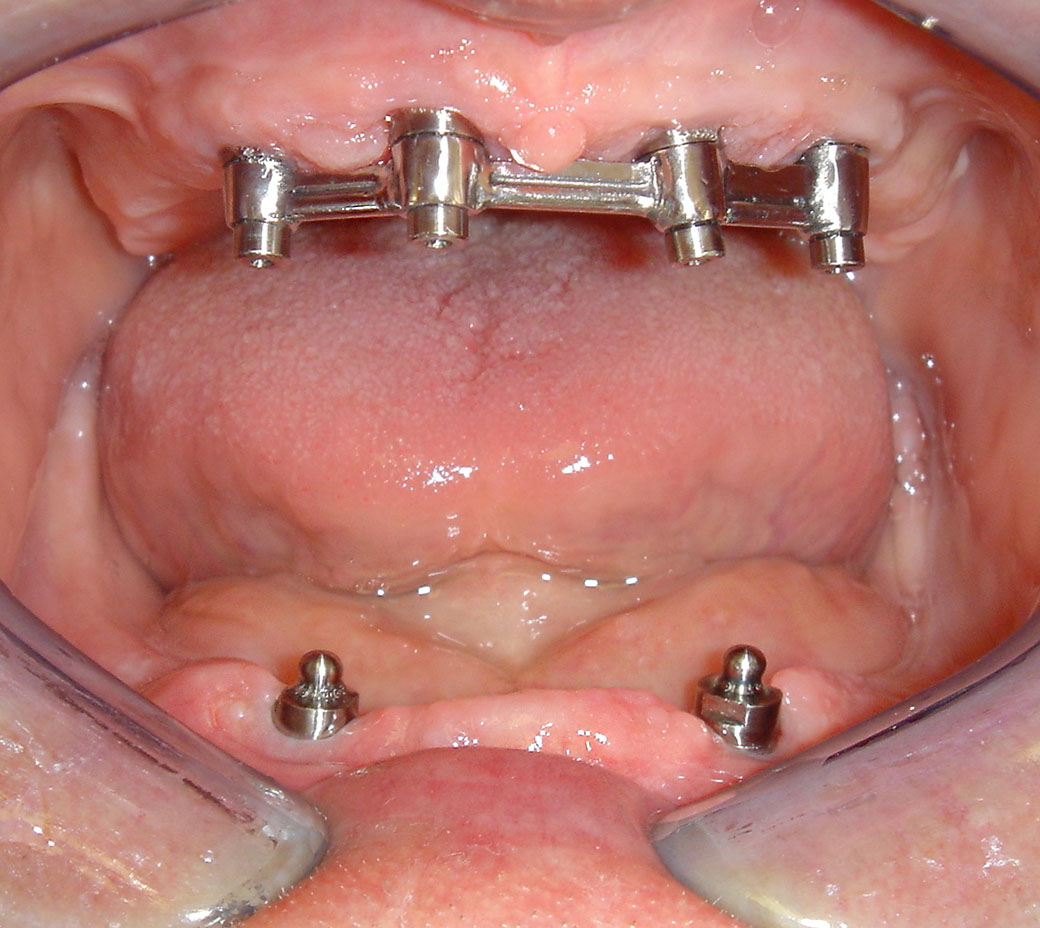

Dank der Geschieben, die kombinierte Zahnersätze einen stabilen und sehr ästhetischen Gebiss verwirklichen